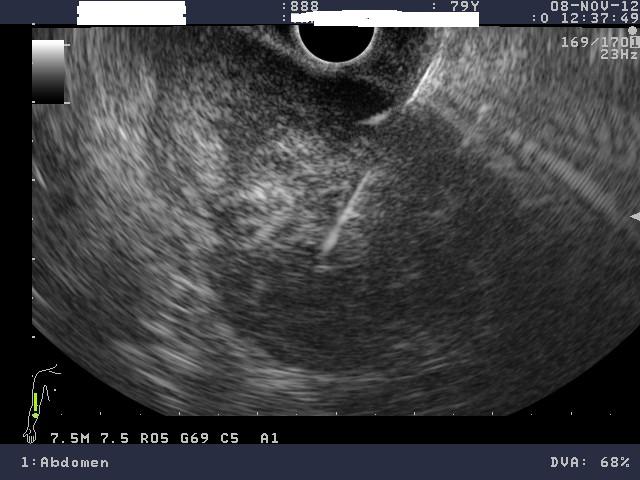

Με τη βοήθεια ειδικού ενδοσκοπίου, που εκτός από την οπτική κάμερα, φέρει στο άκρο του μια κεφαλή υπερήχων, διενεργείται υπέρηχος στα όργανα της κοιλιακής χώρας, μέσα από τον οισοφάγο, τον στόμαχο ή το παχύ έντερο. Επειδή η κεφαλή του υπερήχου είναι σε άμεση επαφή με το όργανο του σώματος που εξετάζεται, η διακριτική ικανότητα του ενδοσκοπικού υπερήχου είναι πολύ υψηλή. Μέσα από το κανάλι του ενδοσκοπίου μπορεί να περάσει λεπτή βελόνα με την οποία λαμβάνονται «βαθιές» βιοψίες από το τοίχωμα του στομάχου ή του εντέρου, αλλά και από γειτονικά όργανα (πάγκρεας, λεμφαδένες).

•    Σε ασθενείς με καρκίνο παγκρέατος όπου γίνεται βιοψία και λήψη υλικού από το πάγκρεας για να τεθεί η διάγνωση, πριν από την έναρξη της θεραπείας.